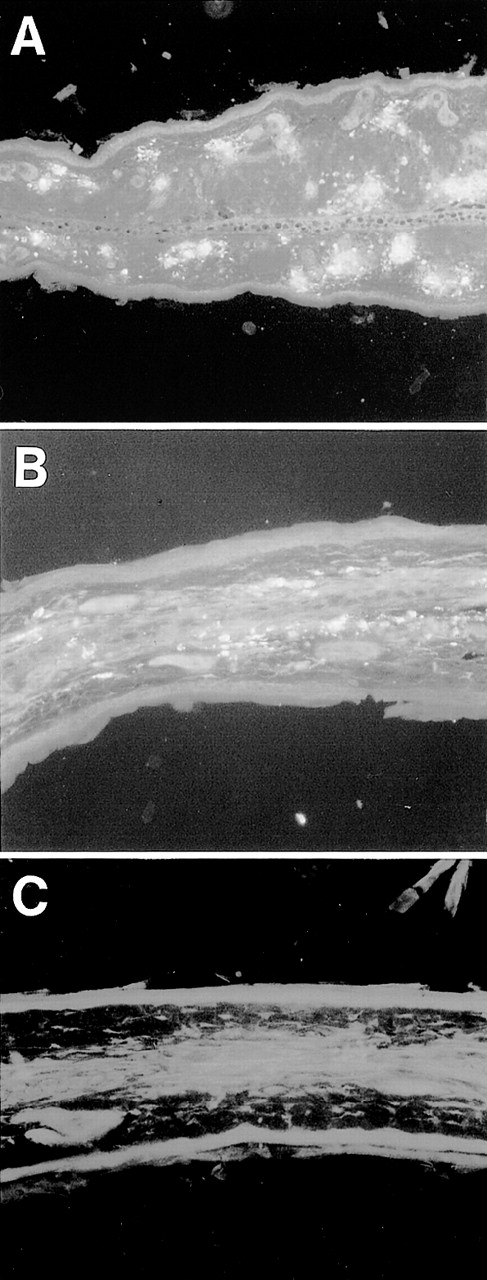

Representative histological appearance of 6-19–induced skin lesions. The sections of the ear from untreated normal mice (A) and 6-19–treated FcRγ+/− (B), FcRγ−/− (C), and TNFβ−/− (D) mice were prepared 12 days after IP injection of 6-19 hybridoma cells. Tissues sections were stained with HE (original magnification × 100). FcRγ+/− mice developed leukocytoclastic vasculitis characterized by the infiltration of PMNs and the extravasation of erythrocytes (B). FcRγ−/− and TNF−/− mice did not develop leukocytoclastic vascular lesions (C and D). Note that in (D), darkly stained cells were melanocytes due to 129 background and that small numbers of PMNs had infiltrated the skin of TNF−/− mice.

Esterase staining of skin of the ear. Ear skin tissues from wild-type and TNFβ−/− mice were fixed in formalin and sections were stained with naphthol AS-D chloroacetate, N,N′-dimethylformamide, and hexazotized new fuchsin, pH 6.3. Arrowheads indicate esterase-positive cells. Estimated numbers of mast cells were 16.4 ± 1.4/field and 18.1 ± 3.2/field, respectively.